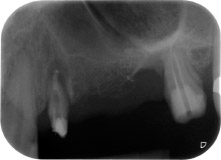

Resultado provisional a los 2 meses

Las figuras 17 y 18 muestran el resultado clínico 2 meses después de la intervención quirúrgica. La pieza 24 tenía una movilidad reducida clase I de Miller y los tejidos blandos no presentaban inflamación. Se evitó el uso de una sonda en este momento para evitar una nueva infección y para no romper la fijación epitelial. El siguiente control se planificó para el momento en el que se reanudara el tratamiento y se colocaran los pilares de cicatrización, 6 meses después de la inserción de los implantes.